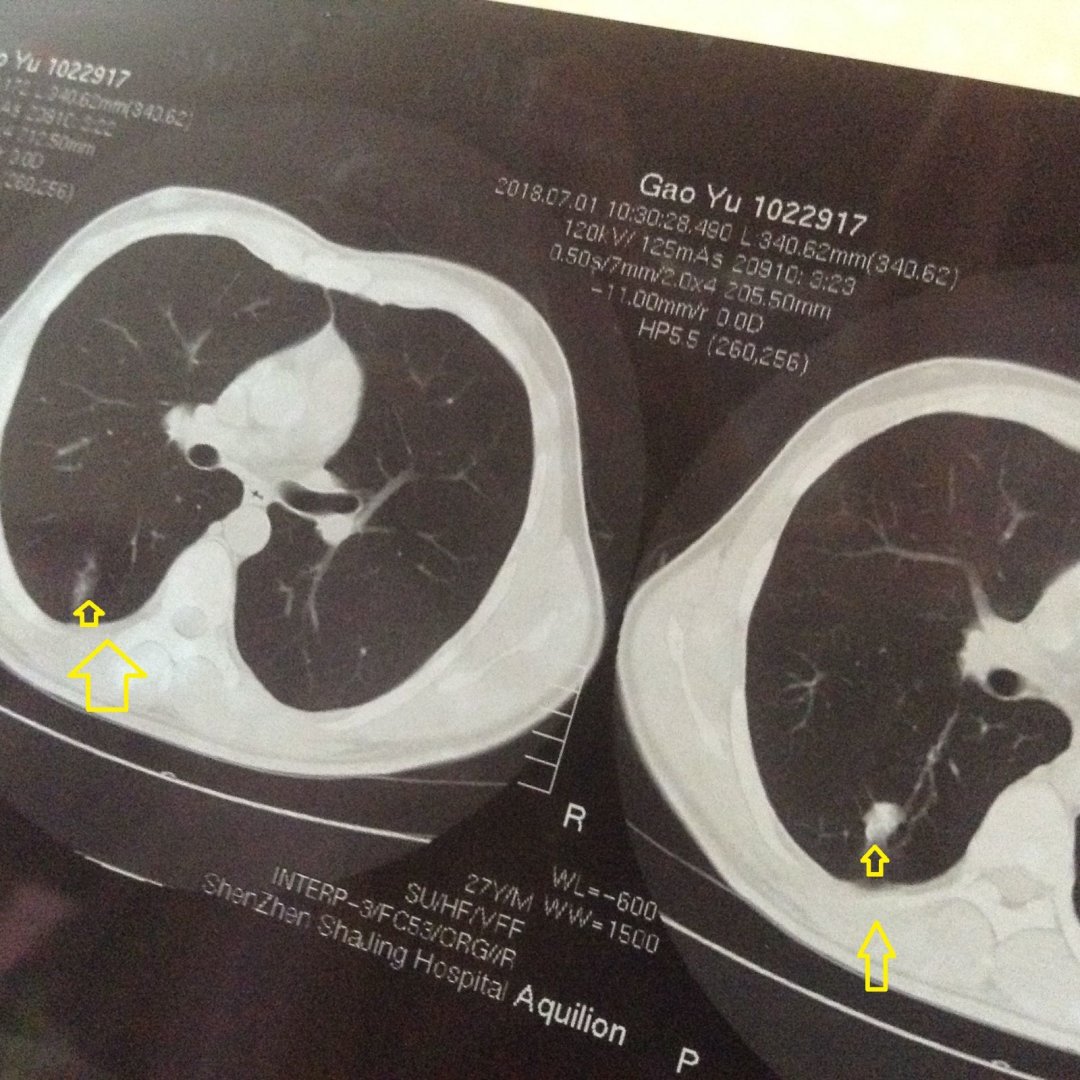

楼主这是肺癌吗?

看片子是肺癌啊